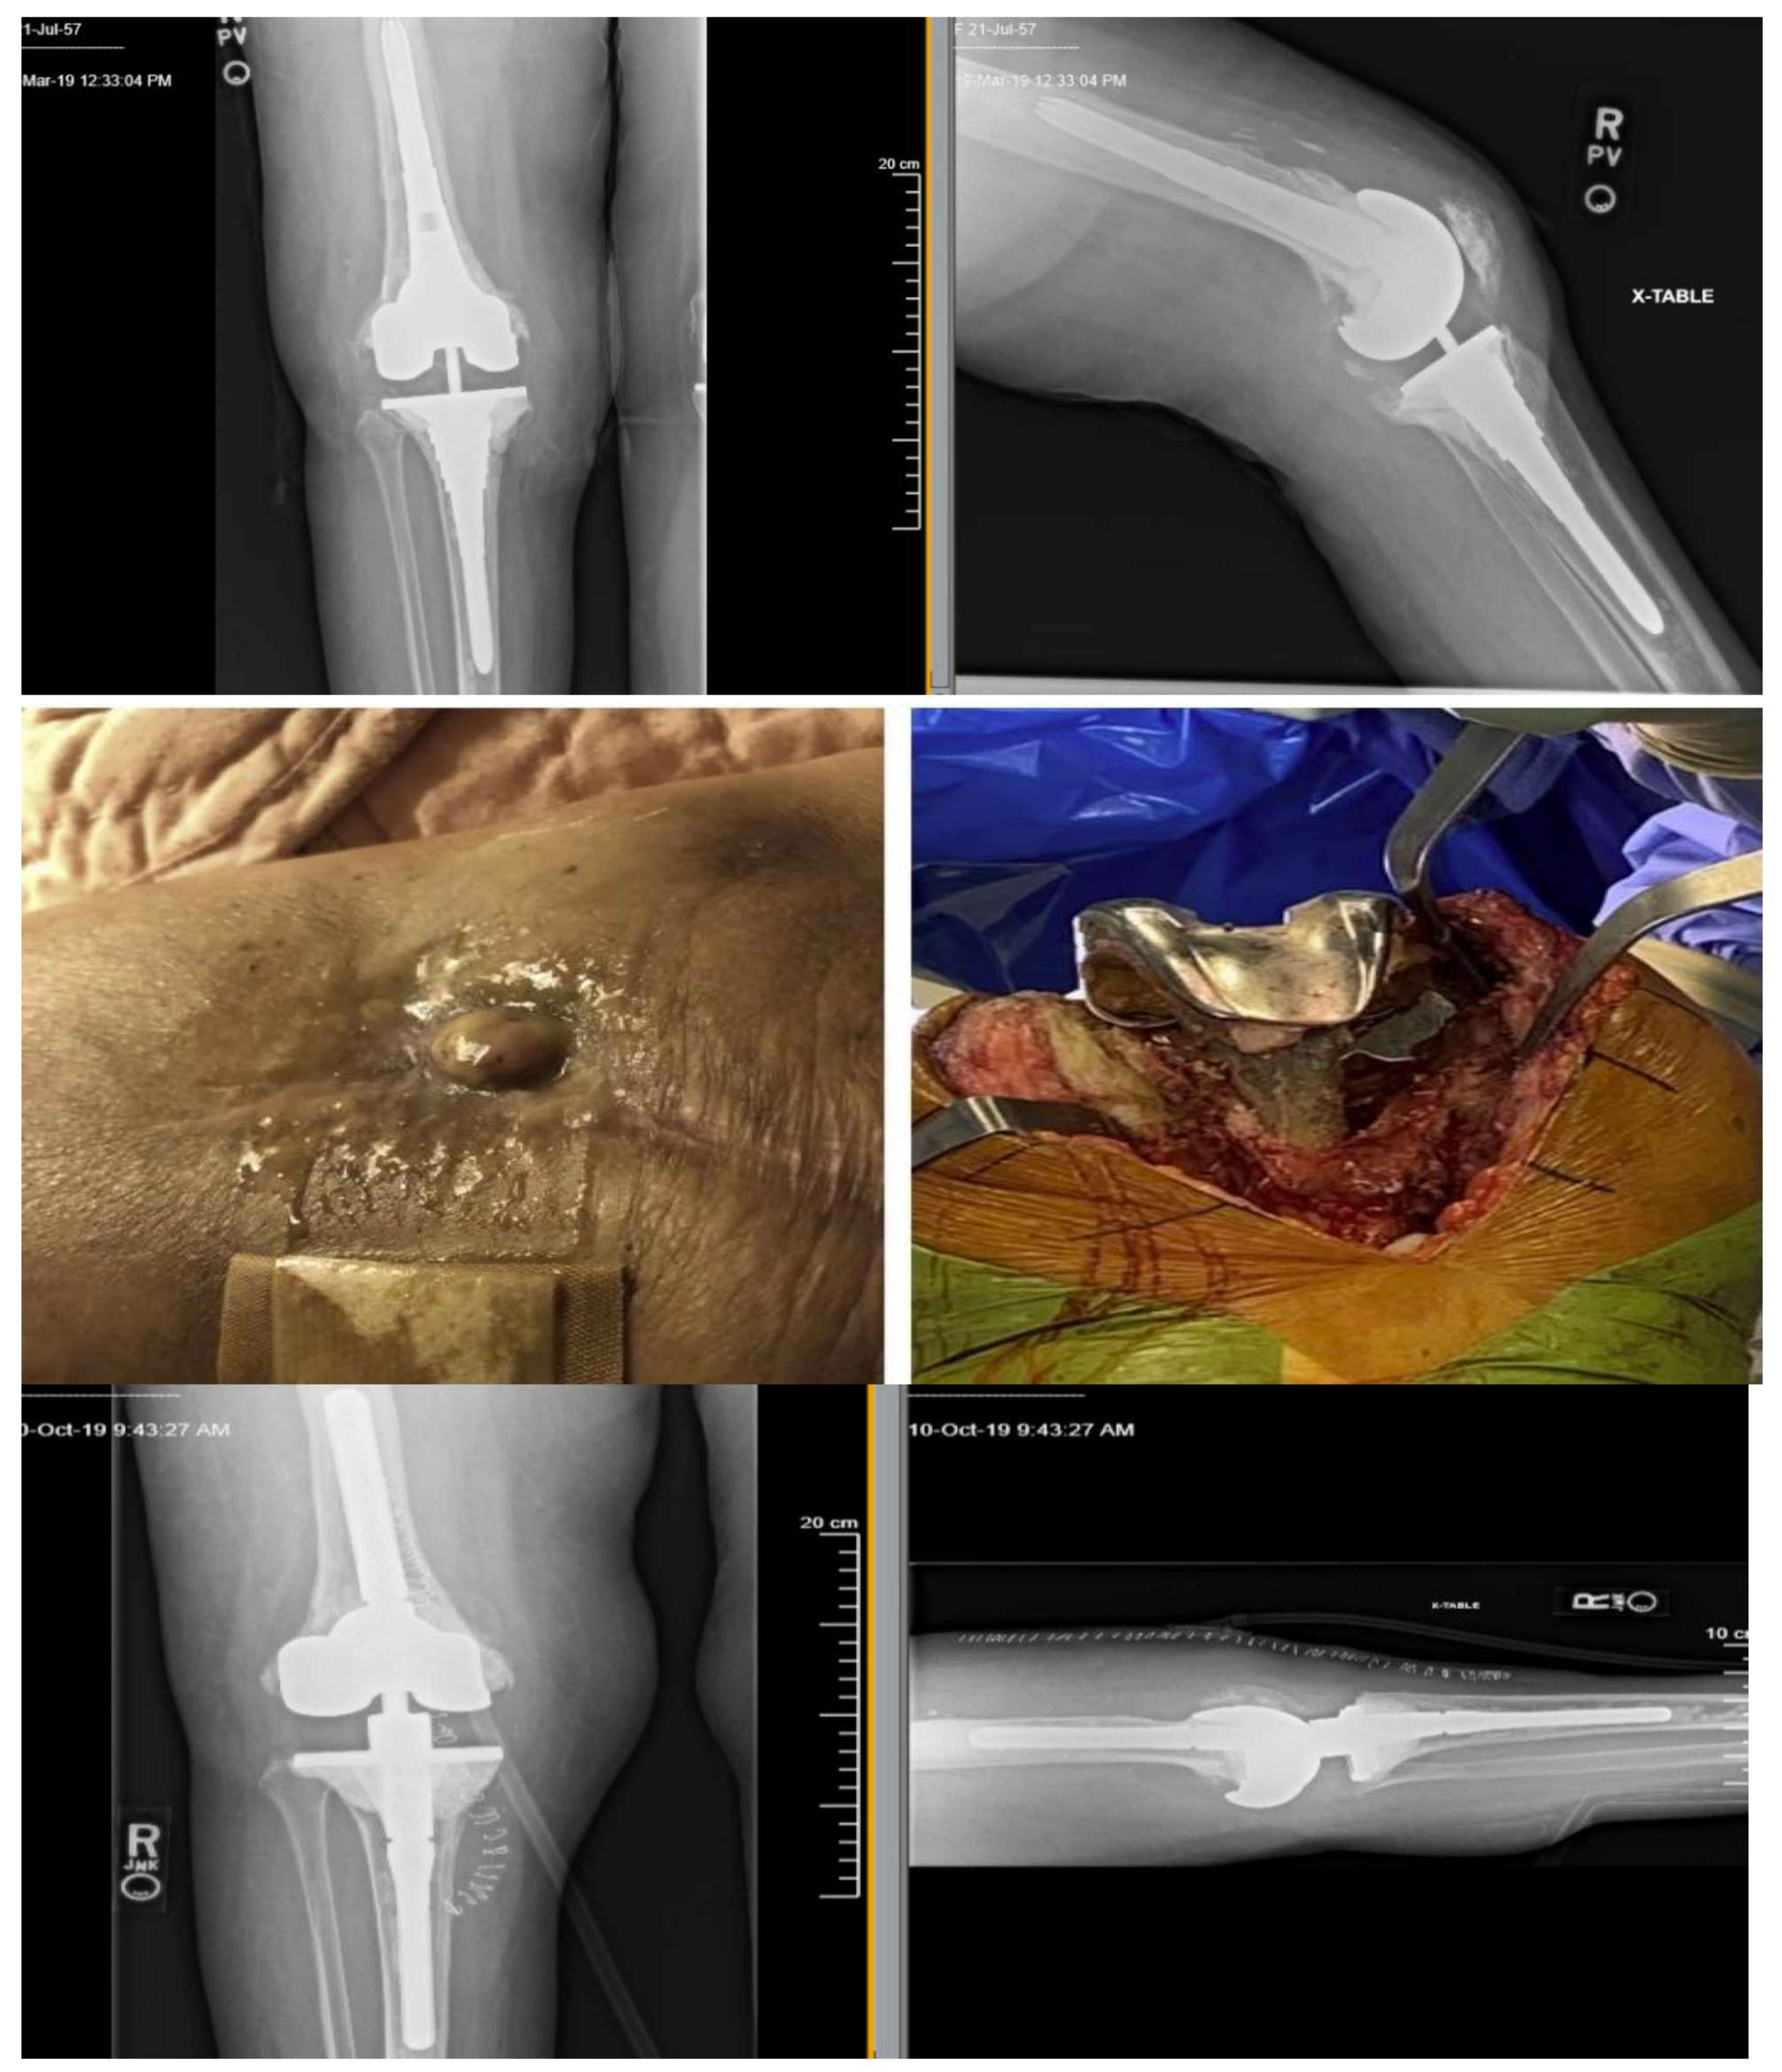

3.1. Clinical History Prior to Phage Therapy

3.1.1. First Course of BT

3.1.2. Second Course of BT